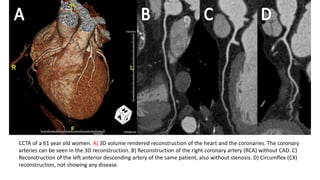

CCTA of a 61 year old women. A) 3D volume rendered reconstruction of the heart and the coronaries. The coronary

arteries can be seen in the 3D reconstruction. B) Reconstruction of the right coronary artery (RCA) without CAD. C)

Reconstruction of the left anterior descending artery of the same patient, also without stenosis. D) Circumflex (CX)

reconstruction, not showing any disease.

CCTA of a61 year old women. A) 3D volume rendered reconstruction of the heart and the coronaries. The coronary arteries can be seen in the 3D reconstruction. B) Reconstruction of the right coronary artery (RCA) without CAD. C) Reconstruction of the left anterior descending artery of the same patient, also without stenosis. D) Circumflex (CX) reconstruction, not showing any disease.